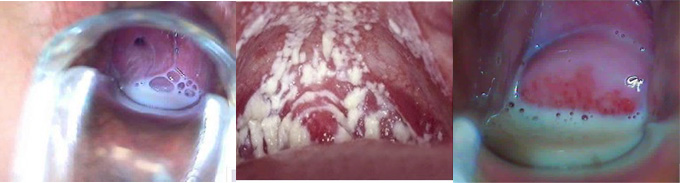

阴道炎是女性朋友中非常常见的一类妇科炎症,严重困扰着广大患者的身心健康,阴道炎根据不同的病因又分为多种不同的类型,那么不同类型的阴道炎各自有什么症状呢?阴道炎图片是什么样的?

1、霉菌性阴道炎:白带增多,呈凝乳状或为片块状,阴道及阴道前庭粘膜高度水肿,覆有白色凝乳状薄膜,呈点状或片状分布,严重的患者小阴唇肿胀粘连常伴有外阴及阴道灼热疫痒,有些患者还伴有尿频、尿急、尿痛等症。

2、细菌性阴道炎:此病患者临床约有10-50%无症状,有症状者典型临床症状为阴道异常分泌物明显增多,呈稀薄均质状或稀糊状,为灰白色、灰黄色或乳黄色,带有特殊的鱼腥臭味。(推荐阅读:治疗阴道炎多久不能同房)

3、滴虫性阴道炎:白带增多,可为稀薄浆液状,灰黄色或黄绿色,有些患者还混有血性,20%白带中有泡沫。外阴有瘙痒、灼热,性交痛亦常见,感染累及尿道口时,可有尿痛、尿急,甚至出现血尿的现象。

4、非特异性阴道炎:非特异性阴道炎常见症状为阴道分泌物增多,呈脓性,浆液性,严重时分泌物有臭味。由于分泌物刺激尿道口,引起尿频、尿痛,阴道内下坠感,灼热,伴有盆腔不运及全身乏力。(推荐阅读:阴道炎容易引发哪些疾病)